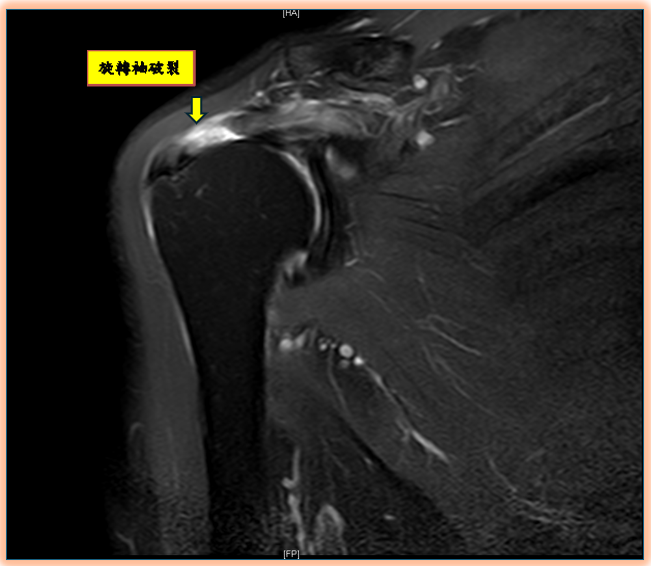

陳昱彰說,當旋轉肌腱因外傷、長期運動或年齡退化變薄失去彈性,就可能出現斷裂,導致手臂無法正常抬舉。常見原因包括:跌倒、車禍、搬重物、長期運動過度使用,或年長者因肌腱退化脆弱,導致旋轉袖破裂。起初常被認為是肌腱拉傷或是五十肩,但許久不癒。起初就應先請骨科醫師來進行正確診斷與治療。診斷上除了理學檢查、X光、超音波,也常用核磁共振(MRI)來確認破裂程度與型態,作為手術規劃。